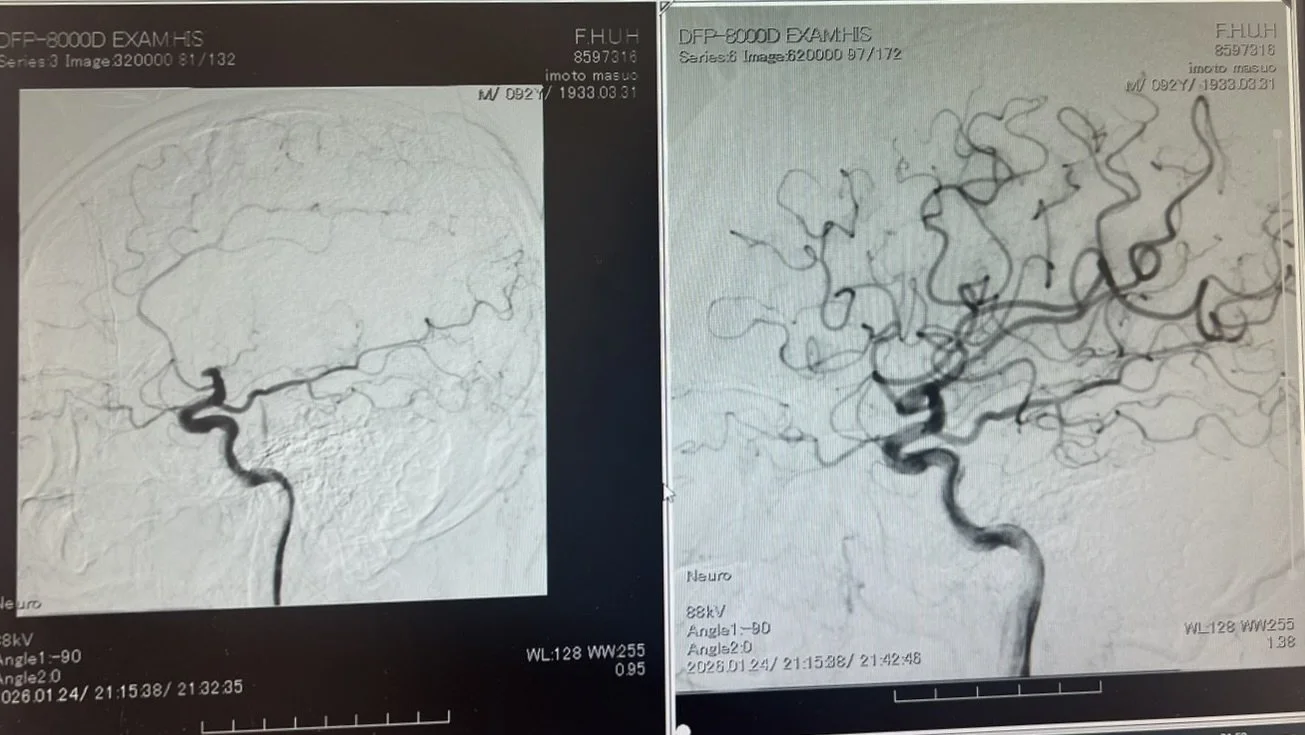

カテーテルは成功した。ドクターが映像を見せながら、説明してくれた。

左後頭部の大きな血管が詰まっている(左写真)。血栓を除去して止まっていた血管に血流が戻った様子(右写真)。